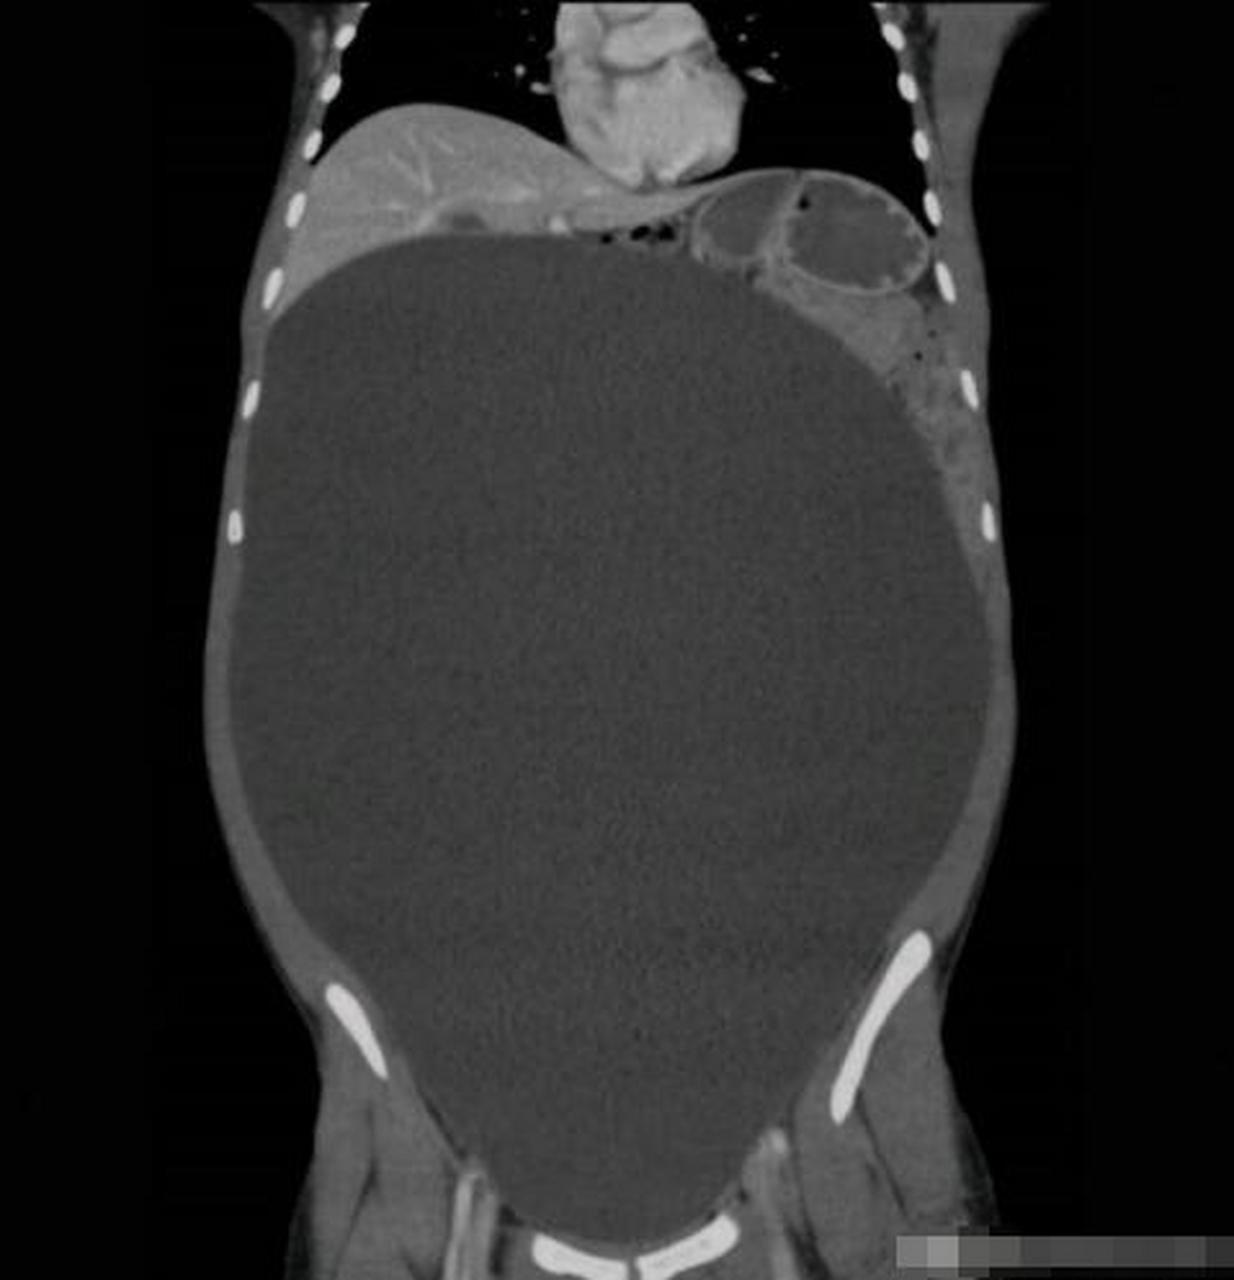

卵巢粘液性囊腺瘤 它属于含粘蛋白上皮性卵巢肿瘤的良性肿块

卵巢浆液性囊腺瘤是最常见的良性上皮性卵巢肿瘤,多表现为边界清车哪